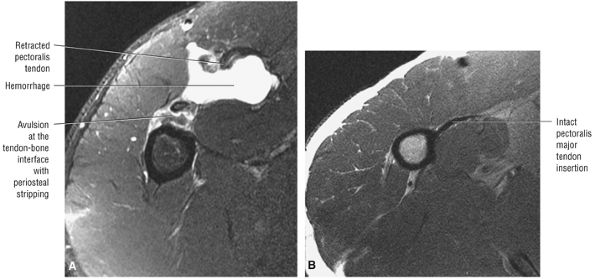

FIGURE 8.102 ● (A) The anterior undersurface of the acromion and the coracoacromial ligament form the coracoacromial arch. The subacromial subdeltoid bursa facilitates the passage of the rotator cuff and proximal humerus under the coracoacromial arch. (B) A superior axial image shows the anterior-to-posterior extent of the coracoacromial (CA) ligament perpendicular to the supraspinatus tendon. The fluid in the subacromial-subdeltoid bursa represents fluid between two serosal surfaces in contact with each other. One serosal surface is contributed by the undersurface of the coracoacromial arch and deltoid, and the other serosal surface is on the bursal side of the cuff.

|

![]() |

FIGURE 8.103 ● Pseudospur. The normal broad attachment of the coracoacromial ligament to the inferior surface of the acromion is shown on (A) T1-weighted coronal oblique and (B) sagittal oblique images. The low-signal-intensity acromial cortex (black arrows) and adjacent coracoacromial ligament and lateral slip of the deltoid attachment (white arrows) give the false impression of a small subacromial spur in the coronal plane. This pseudospur should not be misinterpreted as impingement; otherwise, unnecessary acromioplasties may be performed on patients with a normal coracoacromial ligament attachment and no associated acromial spurs.

-